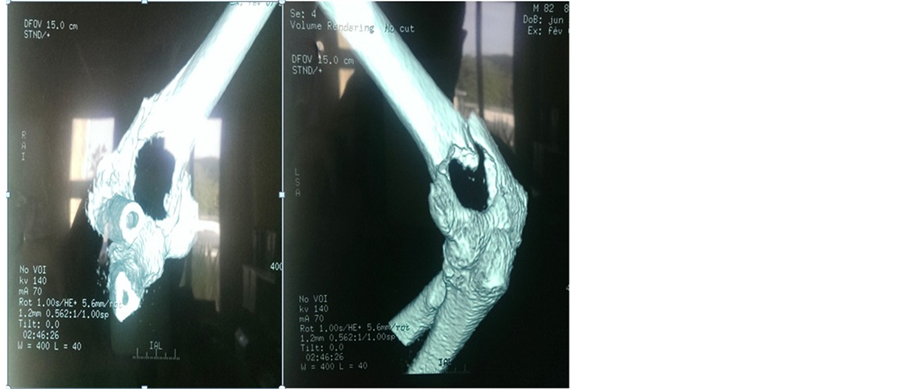

Our patient underwent radiographic assessment is an x-ray radiography face and right elbow profile (Figure 1) with an elbow CT (Figure 2) which has objectified a supra-condylar humerus fracture on a lytic lesion.

Figure 2. Elbow CT image showing a supracondylar humerus fracture on a lytic lesion.